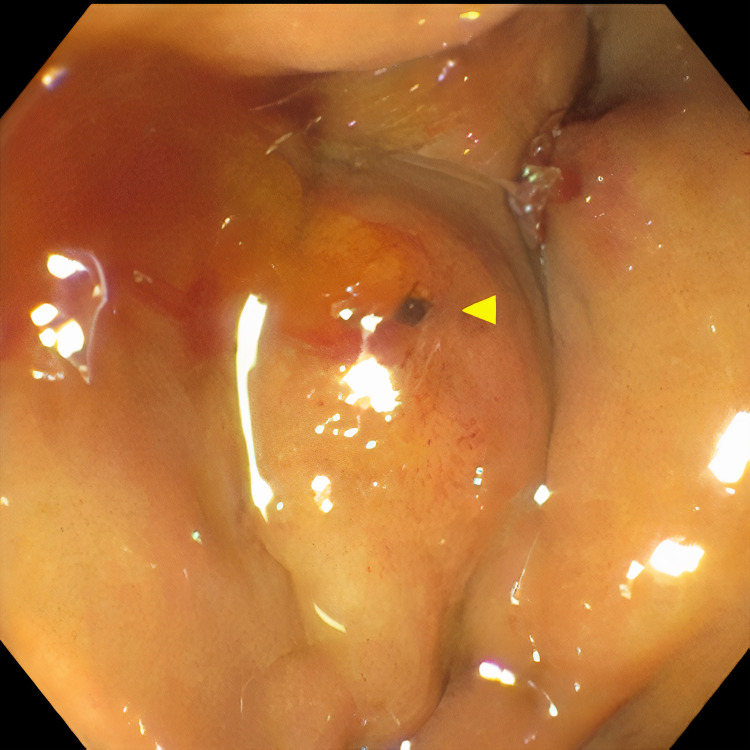

Pertinent labs include elevated white blood cells (13.5×10³/µL), total bilirubin (15.7 mg/dL), direct bilirubin (11.7 mg/dL), aspartate aminotransferase (98 U/L), and alanine aminotransferase (41 U/L). Urinalysis showed tea-colored urine. CT scan of the abdomen and pelvis revealed a collapsed gallbladder with CBD obstruction and bile duct dilation consistent with chronic inflammation. Endoscopic retrograde cholangiopancreatography (ERCP) was then performed which demonstrated cystic duct stone eroding into the common hepatic duct, hence the diagnosis of Mirizzi syndrome was made. Cholangioscopy confirmed the eroding stone, chronic inflammatory changes, and destruction of the bile duct. A cholecystoduodenal fistula with pus drainage was noted in the duodenal bulb. The patient was diagnosed with MS type V according to the ERCP findings. The stone was not amenable to endoscopic removal, but stone debris, clots, and pus (Figures 1–4) were swept. He was referred to the surgical team for cholecystectomy and repair of cholecystoduodenal fistula.